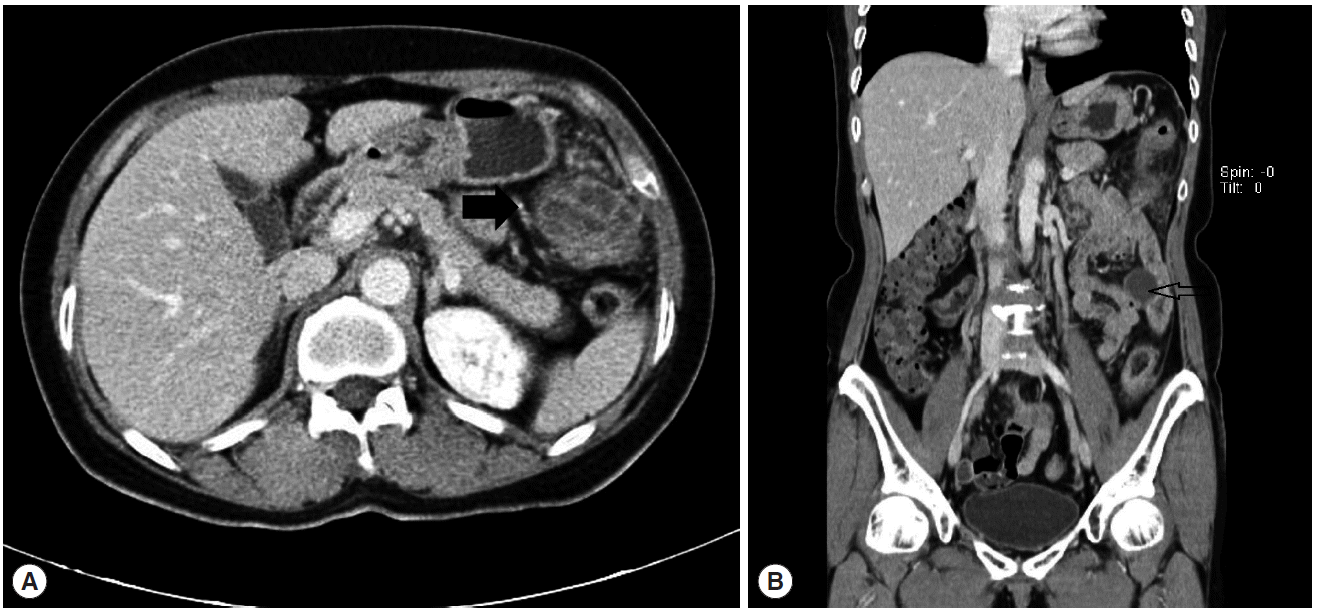

She was admitted after the symptom onset 10 days later (21 October 2011); an abscess was found in the left lower paracolic gutter by abdominal CT and the patient was treated with oral antibiotics. Twenty days after the first CT, on a follow-up CT, 2 additional abscesses were found at the splenic flexure in the left upper quadrant area and the pelvic cavity. Her symptoms did not improve despite the antibiotic therapy.

She was transferred to our hospital on 10 November 2011. At that time, physical examination revealed tenderness in the left lower quadrant of the abdomen. A blood test showed eosinophilia. WBC count was 8,200/μl, and the proportion of eosinophils was 13.8%. CRP was 7.41 mg/dl, and serum electrolytes and liver enzymes were within normal range. An abdominal CT showed 3 abscesses in the left upper quadrant, mesentery, and pelvic cavity. On the 11th hospital day after transfer (21 November 2011), a 4th abdominal CT was performed. Two abscesses were found in the anterior aspect of the distal transverse colon (4 cm) and the interbowel space of the left mid abdomen (3.5 cm) (Fig. 1A, B). The abscess in the pelvic cavity had disappeared. Small bowel series and colonoscopy showed no remarkable findings except a diverticulum at the duodenal third portion.

She was discharged on the 5th postoperative day without additional chemotherapy for parasites. A year later, she did not complain of any symptoms related to the disease, and an abdominal CT finding was normal except the left hemicolectomy (Fig. 4).

CT findings for peritoneal fascioliasis are mesenteric or omental infiltrations, lymph node enlargement, ascites, and mass or thickening of ligamentum teres [32]. Most of these lesions are located in the perihepatic area. It appears that juvenile flukes migrate from the gut mucosa to the liver parenchyma. Imaging of our case showed abscesses in the distal transverse colon and splenic flexure, which was unusual. The location of the abscess on CT images can support this possibility of direct penetration through the intestinal wall.

Fig. 1.

(A) Abdominal CT showing 2 abscesses in the anterior aspect of the distal transverse colon (4 cm, arrow) in the interbowel space of the left middle abdomen (3.5 cm). (B) The coronal view of (A). The arrow indicates the abscess of the interbowel space of the left middle abdomen.

Fig. 4.

No abnormal lesion was observed after 1-year follow-up.

Fig. 1. (A) Abdominal CT showing 2 abscesses in the anterior aspect of the distal transverse colon (4 cm, arrow) in the interbowel space of the left middle abdomen (3.5 cm). (B) The coronal view of (A). The arrow indicates the abscess of the interbowel space of the left middle abdomen.

Fig. 4. No abnormal lesion was observed after 1-year follow-up.